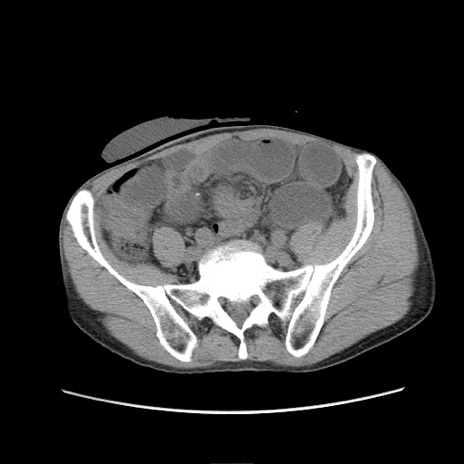

症例11(横断像)

【症例】 60歳代男性

【主訴】 下腹部痛

【現病歴】 本日夜中より下腹部痛の症状認め、受診。

【既往歴】 膀胱癌(膀胱全摘+尿管皮膚瘻術) 、胃癌術後

【身体所見】 BT 35.3℃、PR 58/min、BP 136/98mHg、腹部平坦、軟、腸蠕動音±、ストマ留置あり、左上腹部~正中部に圧痛あり、反跳痛なし。

【データ】WBC 5100、CRP0.01